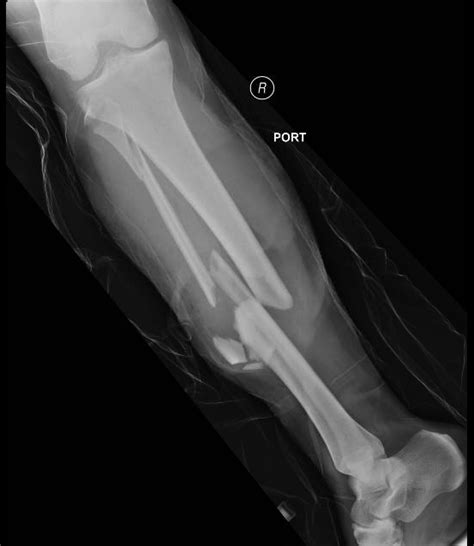

Diagnosing a Tib Fib Fracture involves a combination of physical examination and imaging tests. The diagnostic process typically includes:

• Physical Examination: A healthcare provider will assess the injured leg, checking for pain, swelling, and deformity.

• Imaging Tests: X-rays are the primary imaging tool used to confirm a Tib Fib Fracture. In some cases, additional tests such as CT scans or MRIs may be required for a more detailed view of the fracture.

Tib Fib Fractures are classified based on the location, pattern, and severity of the break. Common classifications include:

Classification Description

Proximal Tib Fib Fracture Occurs near the knee joint.

Midshaft Tib Fib Fracture Occurs in the middle of the tibia and fibula.

Distal Tib Fib Fracture Occurs near the ankle joint.

Open Tib Fib Fracture The bone breaks through the skin, increasing the risk of infection.

Closed Tib Fib Fracture The bone does not break through the skin.